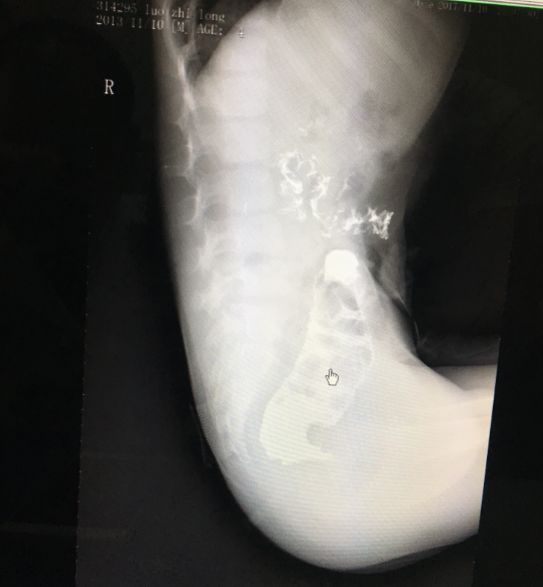

遭受这么多年的折磨,孩子面黄肌瘦,而且粪便排得不畅,堆积在肠子里,都快成石头了,导致了肠梗阻,形成了20厘米的巨结肠!

(片子显示:该男孩因无肛长期导致的巨结肠,足足20厘米 ,要切掉)

巨结肠切掉,建了新的肛门,这名男孩最终解除了痛苦。妈妈再也不用担心他便秘了。